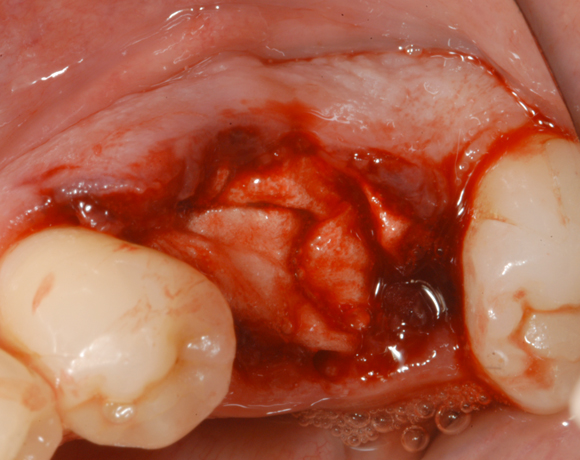

Im vorliegenden Patientenfall wurde eine große Extractionswunde mit einem Remotis® Cone und abschließend mit einem Remotis® Fleece versorgt

Bild 01: Große Extraktionsalveole